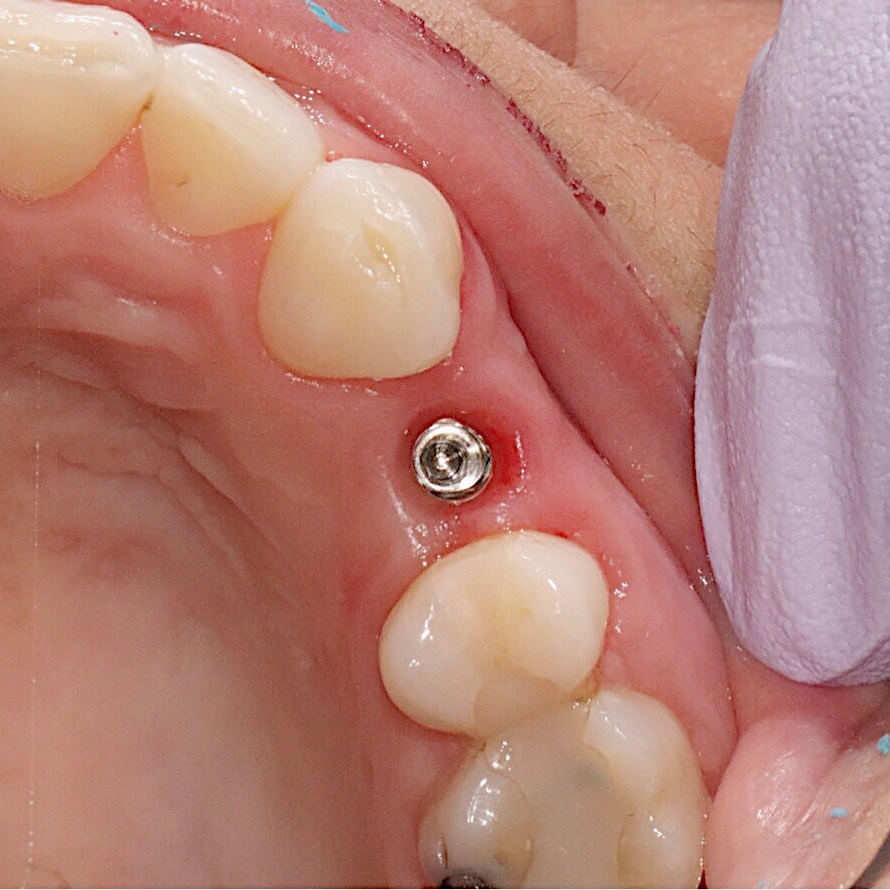

- Option one: place the implant in an area where there is more bone and have the tooth coming in a less ideal position

- Option two: graft the area where you want the implant to be and have the tooth coming in the most ideal position

Option one will lead to an unpredictable outcome as the tooth will not be in the most ideal position in your mouth. This means that food will keep getting stuck around your implant leading to bleeding gums, chronic soreness and discomfort. Having these symptoms long term will lead to implant failure. The final aesthetic result is affected by where the implant is placed.